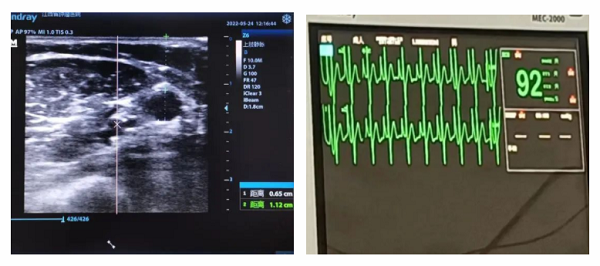

患者丁女士,今年56岁,卵巢癌术后3年复发一年余,为行化疗入住我科(肿瘤内科)。为了保护静脉,避免药物外渗,顺利完成化疗周期,经肿瘤科护士长姚志英带领的 PICC 小组充分评估后,拟经右侧上臂贵要静脉行 PICC 置管术,8月8日,姚志英护士长及专科护士龙灵在超声引导下成功完成首例B超引导下 PICC 置管。术中出血少、患者疼痛感较轻,导管尖端位于上腔静脉,无置管并发症发生。置管成功后,患者及家属表示非常满意。

超声引导下应用改良塞丁格技术行 PICC 置管是目前临床上 PICC 置管的“黄金标准”,通过超声引导的帮助确定位置,深度以及穿刺部位,可置管显示血管解剖结构,全程可见、损伤小、定位准、大大提高了一次性穿刺的成功率、对于临床中常见的肥胖、水肿、反复化疗、静脉血管条件极差的患者,应用B超引导下 PICC 置管术可解决这些难题。以往血管条件差的患者都要到宜春、南昌才能完成,现在超声引导下 PICC 置管在县域内开展,节约了患者的就诊时间,减少了患者的经济负担。

对于需要长期静脉输液的患者,如长期住院治疗导致血管破坏等;缺乏外周静脉通路倾向、肥胖、血管不明显的患者,如大面积烧伤患者血管条件差等;输注刺激性药物的患者,如化疗药物等;输注高渗性液体,如胃肠外营养液、脂肪乳、甘露醇;需要长期行家庭静脉治疗的患者等都需要行 PICC 导管输注,以往常规方法的盲穿PICC需要有看得见、摸得着的血管,而超声引导下 PICC 其可以直观地显示血管的解剖结构,具有实时引导、全程可见、缩短穿刺时间、减少并发症、留置位置较隐蔽不影响患者外出形象等优势,不仅能减轻穿刺患者的痛苦,同时为护理人员提供了一种安全有效的输液途径,做到“心中有数”,姚志英护士长说道。